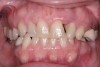

Fig 1. After a thorough examination, it was determined that this patient needed extraction of the maxillary teeth and restoration with an implant-retained full-arch prosthesis.

Figure 1